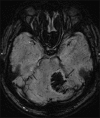

Materials and methods: All patients referred for a complete brain magnetic resonance imaging (MRI) between March 2010 and March 2011 at our institution had SWI as part of routine MRI (T1, T2, and diffusion imaging). Retrospective study of 62 consecutive patients with acute arterial infarct was evaluated for the presence of macroscopic hemorrhage, petechial micro-bleeds, dark middle cerebral artery (MCA) sign and prominent vessels in the vicinity of infarct.

Results: SWI was found to detect hemorrhage not seen on other routine MRI sequences in 22 patients. Out of 62 patients, 17 (10 petechial) had hemorrhage less than 50% and 5 patients had greater than 50% area of hemorrhage. A "dark artery sign" due to thrombus within the artery was seen in 8 out of 62 patients. Prominent cortical and intraparenchymal veins were seen in 14 out of 62 patients.

Conclusions: SWI has been previously shown to be sensitive in detecting hemorrhage; however is not routinely used in stroke evaluation. Our study shows that SWI, by virtue of identifying unsuspected hemorrhage, central occluded vessel, and venous congestion is additive in value to the routine MR exam and should be part of a routine MR brain in patients suspected of having an acute infarct.